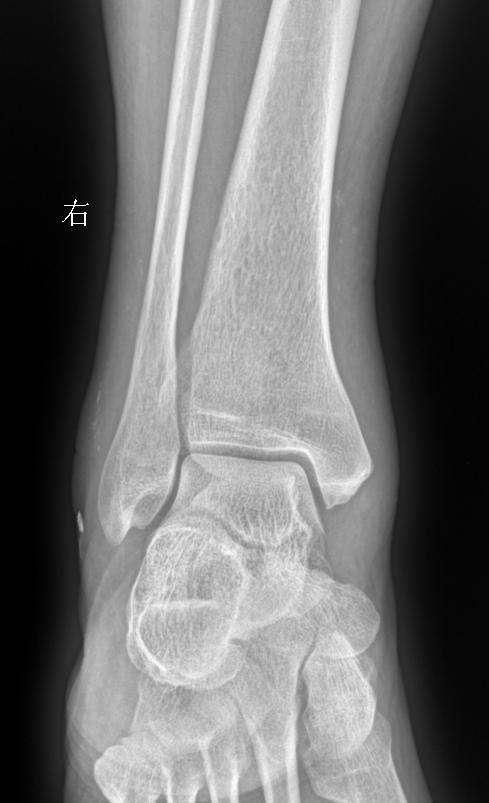

男 71 外伤疼痛20天 软组织肿胀

2025-11-27 03:52